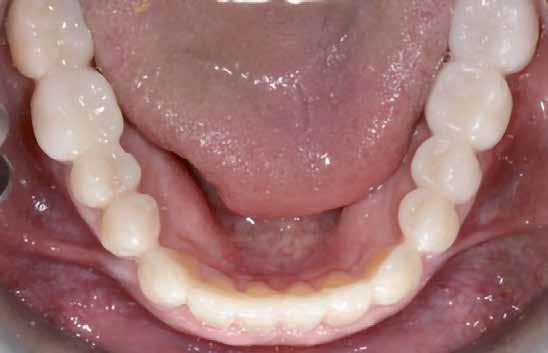

A fogazat elhasználódása alatt azoknak a degeneratív folyamatoknak az összesített hatását értjük, melyeken az élet során a szervezet keresztülmegy. Ezek lehetnek a fogérintkezések közben fellépő mechanikai erők (abrázió, attríció), endogén vagy exogén eredetű savas közegek által kiváltott kémiai behatások (erózió), kariogén baktériumok által okozott pathológiás folyamatok és parodontális elváltozások, valamint iatrogén ártalmak.

A felnőtt páciensek kezelése során általában egyszerre több ellátásra szoruló elváltozást is diagnosztizálhatunk: hiányzó fogak, kopott fogazat, esetleg régi, nem megfelelő, sérült fogpótlások, rendellenes helyzetben lévő fogak stb… Ezen páciensek kezelésekkel kapcsolatos kérései mindig az esztétikai vagy a rágással kapcsolatos kívánságaik kielégítését szolgálja. A kezelések során a fogorvosoknak nem csak a páciensek kéréseinek teljesítésére, hanem ezzel egyidejűleg a fogazat általános megjelenésének és funkciójának lehetőség szerinti javítására is törekedniük kell. Mindemellett a lehető legtöbb saját foganyag megőrzését és az évek során elvesztett kemény- és lágyrészek pótlását (pl.: hiányzó fogak, sorvadt állcsontgerinc, lágyszöveti defektusok) is szem előtt kell tartaniuk, úgy, hogy közben egy hosszú távon fenntartható eredményekkel járó kezelési tervet állítanak össze. Ezek mindig összetett esetek. Annak érdekében, hogy a fentiekben megfogalmazott összes kezelési célt teljesíteni tudjuk, interdiszciplináris megközelítésre van szükség. Az ilyen komplex rehabilitációs kezeléseket „fogászati megfiatalításnak” nevezzük. Ezeknek a beavatkozásoknak lényege az elhasználódott fogazat biológiai szempontokat figyelembe vevő minimál invazív módon történő helyreállításában rejlik, mely folyamat végére a páciensek fogai visszanyerhetik fiatalkori megjelenésüket.

A rehabilitációs kezeléseknek a célja, hogy a páciensek a lehető leghosszabb időn keresztül képesek legyenek mosolyogni és rágni. A protetikai kezeléseket végző fogorvosoknak helyre kell tudni állítaniuk a fogívek szabályos lefutását és az alsó és felső fogív között megfelelő interokkluzális érintkezéseket kell létrehozniuk. Így lehet csak az ellátás befejezését követően elért végeredmény biológiai szempontokat figyelembe vevő esztétikáját, funkcionális megfelelőségét, hosszú távú fenntarthatóságát biztosítani.

A preprotetikai fázisban el kell látnunk a diagnosztizálásra került kórfolyamatokat, megfelelő pozícióba kell állítanunk a megtartani kívánt fogakat, pótolnunk kell az elvesztett csontállományt, valamint gondoskodnunk kell az íny megfelelő állapotáról. Ha szükség van rá, úgy a foghiányok pótlására szolgáló dentális implantátumok is ebben a fázisban kerülnek behelyezésre. Általánosságban elmondható, hogy azokat a kezeléseket, amelyek befejezése biológiai okok miatt hosszú időt vesz igénybe (pl.: fogszabályozás, csontpótlás, implantáció), a lehető leghamarabb érdemes elkezdeni.

A fogszabályzó kezelések egyik legfontosabb célja, hogy elérjük a lehető legharmonikusabb interokkluzális fogérintkezéseket, továbbá az állcsont relációs helyzetének frontális és szaggitális síkban is megfelelőnek kell lennie. A fogszabályzás befejezésekor a fogpozícióknak nem orthodonciai, hanem protetikai szempontok szerint kell ideálisnak lenniük. Az Invisalign ClinCheck szoftver (Align Technology) segítségével a protetikus az orthodontussal együtt meg tudja határozni azokat a végső fogpozíciókat, amelyek a lehető legjobb végeredmény biztosításához elengedhetetlenek. Bizonyos klinikai paramétereket, mint a fogak klinikai koronájának nagyságát, az egyes fogak fogíven belüli optimális pozícióját, a fogívek egymáshoz viszonyított helyzetét, a fogak között látható rések nagyságát, a frontfogak tengelyének dőlését, az overjet és overbite mértékét már a kezelések megkezdése előtt pontosan definiálni kell. Ezeket az adatokat viszont csak a tervezett végleges fogpótlás ismeretében lehet meghatározni, ezért van szükség az orthodontus és a protetikus szoros együttműködésére.